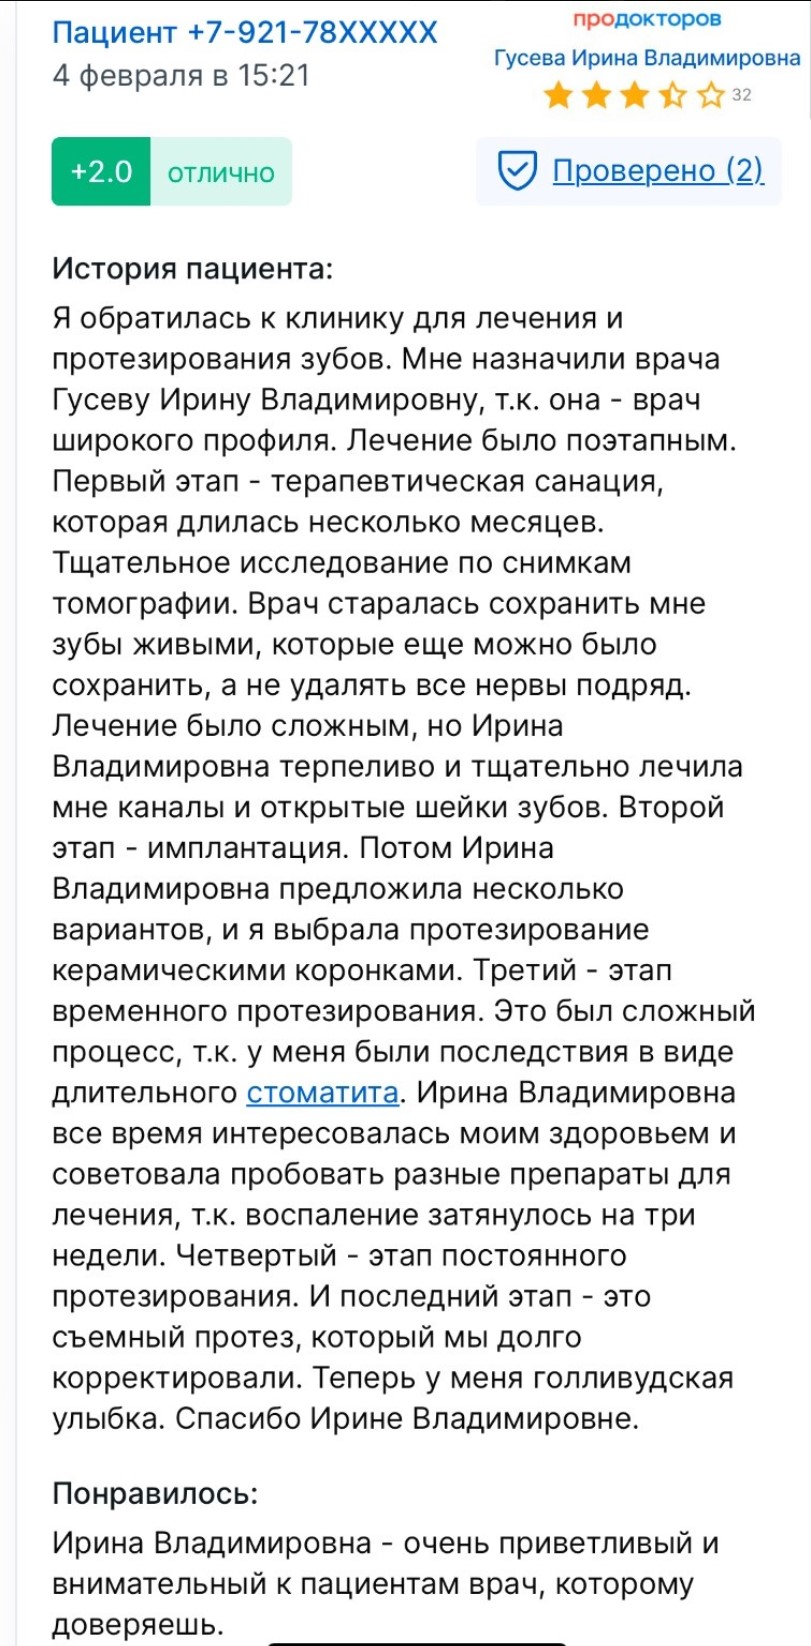

Ирина Гусевастоматолог-терапевт, имплантолог, ортопед

Ирина Гусевастоматолог-терапевт, имплантолог, ортопед